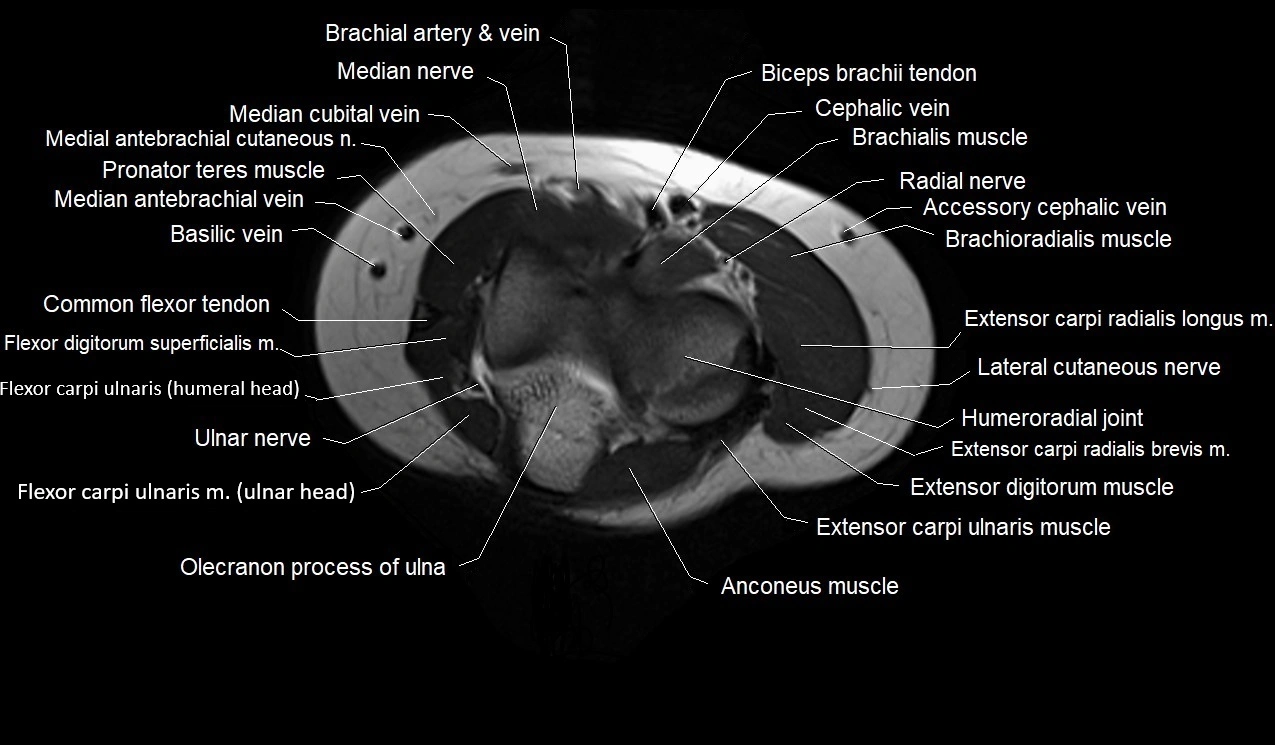

MRI images

image